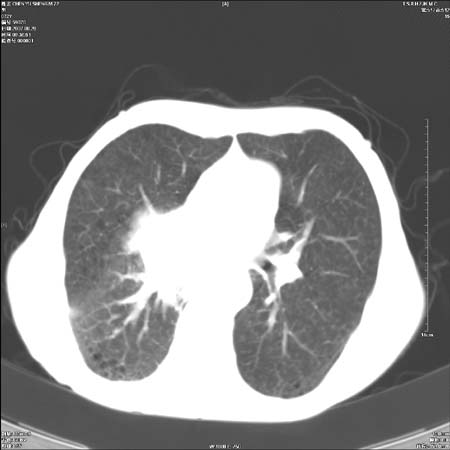

男性,72岁,既往肺结核,今复查。无前片对比。

右侧中央型肺癌伴中叶不张可能性大,建议增强扫描.右上肺陈旧性肺结核.慢性支气管炎伴肺气肿.右侧少量胸腔积液.

右侧中央型肺癌伴中叶不张可能性大,建议纤支镜检查.右上肺陈旧性肺结核.肺气肿。

典型右肺中心型肺癌

右侧中央型肺癌伴肺不张可能性大,建议增强扫描.右上肺陈旧性肺结核.慢性支气管炎伴肺气肿.右侧少量胸腔积液.

右肺中心型肺癌

右侧中央型肺癌.上肺陈旧性肺结核.

1右侧中央型肺癌伴中叶不张2右侧少量胸腔积液3右上肺陈旧性肺结核

1.右肺中心性肺癌并右肺中叶综合征2。右侧胸腔少量积液3。右肺上叶结核球已钙化,4。慢支伴肺气肿

右侧中央型肺癌伴中叶不张可能性大,建议纤支镜检查.右上肺陈旧性肺结核.肺气肿。

右侧中央型肺癌伴中叶不张可能性大,建议增强扫描.右上肺陈旧性肺结核.慢性支气管炎伴肺气肿.右侧少量胸腔积液.

右侧中央型肺癌伴中叶不张

右肺中央型肺癌伴右肺中叶不张。

右上肺陈旧性肺结核。

支持右肺中心型肺癌并中叶不张,右上肺陈旧性肺结核钙化,右侧少量胸腔积液。

支持右侧中央型肺癌伴中叶不张可能性大,建议增强扫描.右上肺陈旧性肺结核.慢性支气管炎伴肺气肿.右侧少量胸腔积液.

支持 1右侧中心型肺癌伴中叶不张2右侧少量胸腔积液3右上肺陈旧性肺结核4双肺局限性肺气肿

1,右侧中央型肺癌.

2,右上肺陈旧性肺结核.

1.右侧中央型肺癌伴中叶不张,建议纤支镜检查.

2.右上肺陈旧性肺结核.

3.肺气肿。

4.右侧少量胸腔积液.

右侧中央型肺癌伴中叶不张并纵隔淋巴结增大,建议增强扫描.右上肺陈旧性肺结核.慢性支气管炎伴肺气肿.右侧少量胸腔积液。

右肺中心型肺癌并肺不张,陈旧性肺tb.慢支,肺气肿.

陈旧性肺结核.慢性支气管炎伴肺气肿,中央型肺癌伴中叶不张。

右侧中央型肺癌伴中叶不张可能性大;右上肺陈旧性肺结核.慢性支气管炎伴肺气肿

陈旧性结核是存在,但真正致命的却是右侧中心型肺癌。